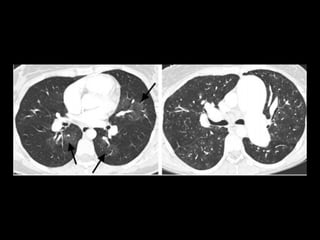

Tomografia computadorizada

Angiotomografia dos vasos pulmonares com TCMD

e reconstruções com filtro de alta resolução;

Mede-se o tronco da pulmonar próximo à sua

bifurcação e lateralmente à aorta ascendente;

Em adultos: até 29 mm;

Sensibilidade: 69-87%;

Especificidade: 89-100%.

Um diâmetro da artéria pulmonar > aorta

ascendente: sensibilidade de 70% e especificidade

de 92% no diagnóstico de HAP;

Achados parenquimatosos: dependem da etiologia

e mecanismo da hipertensão:

Perfusão em mosaico, vidro fosco, espessamento

septal e nódulos centrolobulares.

Derrame ou espessamento pleural, e, em pacientes

com HAP grave, pequeno derrame pericárdico.

HAPI: imagem: Rx e TC

Aumento do calibre dos vasos pulmonares;

Afilamento dos vasos e oligoemia;

Sinais de cardiomegalia direita;

Tortuosidade dos vasos pulmonares periféricos;

Em alguns pacientes: nódulos centrolobulares em

vidro fosco(hemorragia, congestão vascular ou

depósitos de colesterol);

Padrão em mosaico: em alguns pacientes;